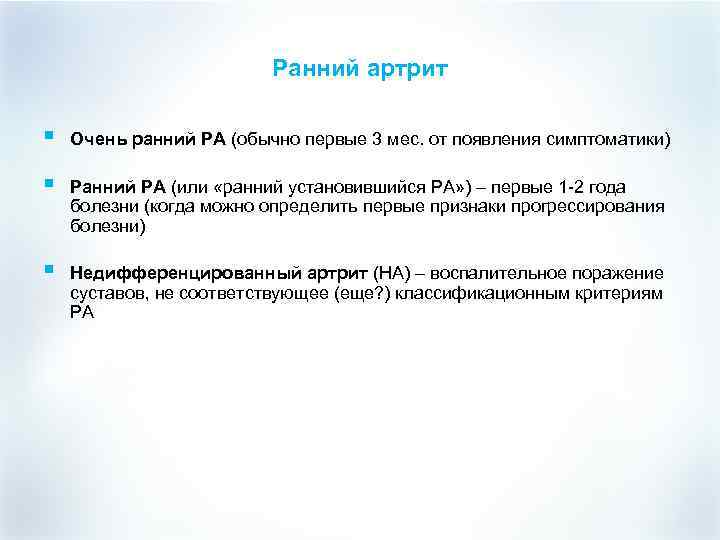

Ранний артрит § Очень ранний РА (обычно первые 3 мес. от появления симптоматики) § Ранний РА (или «ранний установившийся РА» ) – первые 1 -2 года болезни (когда можно определить первые признаки прогрессирования болезни) § Недифференцированный артрит (НА) – воспалительное поражение суставов, не соответствующее (еще? ) классификационным критериям РА

Ранний артрит § Очень ранний РА (обычно первые 3 мес. от появления симптоматики) § Ранний РА (или «ранний установившийся РА» ) – первые 1 -2 года болезни (когда можно определить первые признаки прогрессирования болезни) § Недифференцированный артрит (НА) – воспалительное поражение суставов, не соответствующее (еще? ) классификационным критериям РА

Классификация раннего артрита § § При этом выделяют: - «Очень ранний РА» – заболевание с длительностью симптоматики до 3 месяцев, поскольку в течение этого периода можно сделать вывод о стойкости артрита (этот период можно считать потенциально обратимым состоянием), в ряде случаев граница очень ранней стадии проводится в районе 6 месяцев, учитывая частые случаи постепенного развития симптоматики; -ранний РА (или «ранний установившийся РА» ) – первые 1– 2 года болезни (когда можно определить первые признаки прогрессирования болезни, такие как наличие или отсутствие типичного эрозивного процесса в суставах); -недифференцированный артрит (НА) Практический смысл ранней диагностики состоит в обосновании раннего назначения базисных противовоспалительных препаратов (БПВП).

Классификация раннего артрита § § При этом выделяют: - «Очень ранний РА» – заболевание с длительностью симптоматики до 3 месяцев, поскольку в течение этого периода можно сделать вывод о стойкости артрита (этот период можно считать потенциально обратимым состоянием), в ряде случаев граница очень ранней стадии проводится в районе 6 месяцев, учитывая частые случаи постепенного развития симптоматики; -ранний РА (или «ранний установившийся РА» ) – первые 1– 2 года болезни (когда можно определить первые признаки прогрессирования болезни, такие как наличие или отсутствие типичного эрозивного процесса в суставах); -недифференцированный артрит (НА) Практический смысл ранней диагностики состоит в обосновании раннего назначения базисных противовоспалительных препаратов (БПВП).